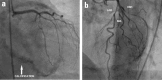

Massive, ring-shaped pericardial calcification of atrioventricular groove